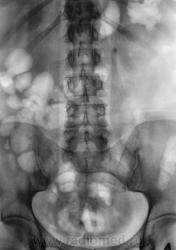

Начинаю описывать в\в урографию и...где же тень конкремента? ЕЕ на прежнем месте нет....ЧЛС слева не расширена, дополнительных теней или "плюс-тени" явно не просматривается....

Начинаю мужичка "трясти как грушу"..."всплывает" обзорная урография за сентябрь 2009 года...да, там низковато захвачено...но зона конкремента попала...а его....НЕТ!!!!!!!!!!!!!!!! Не мог же он вырасти за каких то полгода до ТАКИХ размеров.

В голову лезут всякие бредовые идеи...и одна из них - инородное тело (суммация тени на тень почки) типа животной косточки.....Начинаю вновь "трясти" мужичка и...выплывает полный рот протезов и...."кушал кролика за сутки-двое до снимка" (на котором тень конкремента)....сомнения возрастают, тем более тень уж больно смахивает на короткую трубчастую кость из лапки мелкого животного (к примеру)......

Вызываю мужичка вновь из отделения и делаю прицельные снимки, в т.ч. с компрессией, левой почки....сомнения в наличии камня остаются...

Ночь сплю не очень хорошо...мучают сомнения...с утра вызываю мужичка вновь...делаю контрольные прицельные снимки...

И вот он "красавец" - оказывается - он как маятник ходит из нижней чашки в лоханку, периодически вызывая нечетко выраженную колику, зато с микро- и макрогематурией....

Анализ - ноги ошибки "выросли" еще их первой обзорной урограммы, выполненной, мягко говоря, не совсем корректно....